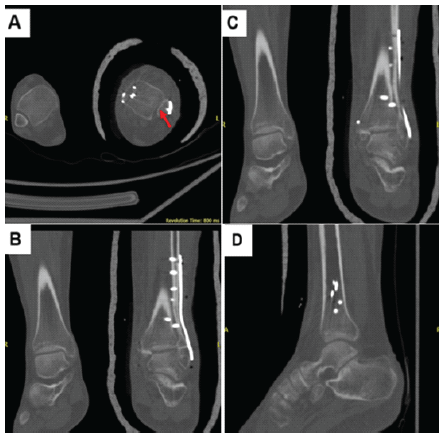

Subsequently, through a medial ankle approach, the bent medial malleolar screws were removed. Debridement of fibrous tissue and periosteum from the fracture site was performed. Fixation was achieved using a tension band technique with additional K-wire stabilization. The surgical site was washed, wounds closed in layers, and a below-knee slab was applied post-operatively. However, follow-up imaging 1 week later demonstrated anterior subluxation of the syndesmosis (red arrow) (Fig. 4).

Figure 4: Follow-up computed tomography scan showing anterior subluxation (red arrow) of the syndesmosis. Axial (a), coronal (b and c), and sagittal (d) views.